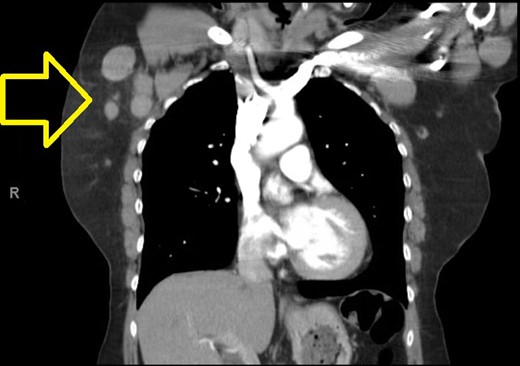

A computed tomographic (CT) scan of her chest with contrast revealed moderate right axillary lymphadenopathy and a lesion in the upper outer quadrant of the right breast measuring 1.3 × 1.2 cm (Fig. 1). A positron emission tomography (PET) scan showed a small intense focus on the right lateral breast consistent with carcinoma, significant right axillary lymphadenopathy and intense fluorodeoxyglucose hypermetabolic activity consistent with metastatic spread. Additionally, enlarged lymph nodes extending along the upper chest wall just inferior to the subclavian vessels and posterior to the pectoralis muscles were seen. A needle biopsy of the mass revealed an extensive involvement of poorly differentiated infiltrating carcinoma (Fig. 2). The tumor showed large nuclei with eosinophilic cytoplasm and prominent nucleoli consistent with apocrine differentiation (Fig. 3). There was a significant inflammatory response to the infiltrating tumor noted. No lymphovascular invasion was identified within the core biopsies. The specimen was estrogen and PR negative as well as HER-2/neu negative.

Photomicrograph: apocrine differentiation and inflammatory response.